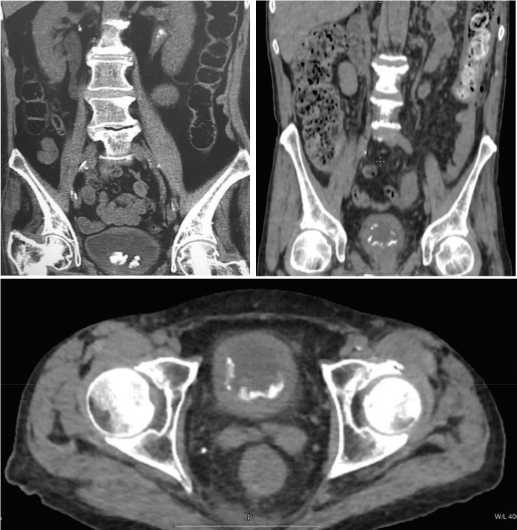

По данным КТ органов малого таза у всех пациентов выявлено утолщение стенки наполненного мочевого пузыря свыше 4 мм,инкрустация слизистой на различных по площади участках; наличие конкрементов в просвете мочевого пузыря,как фиксированных, так и свободно лежащих (рис. 2).

Рис. 2. Компьютерная томография. Картина конкрементов в просвете мочевого пузыря при инкрустирующем цистите

Fig. 2. Computed tomography. The picture of concretions in the lumen of the bladder with encrusting cystitis